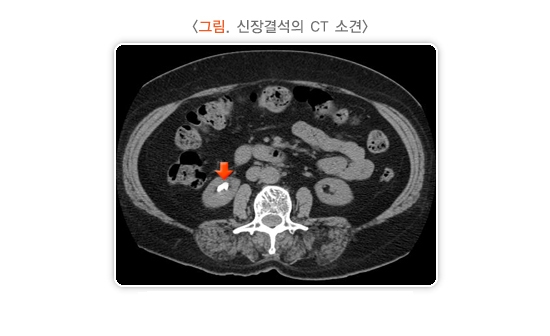

1) 복부 컴퓨터단층촬영(Computed Tomography, CT)

급성기의 신장결석과 비뇨기계 결석을 찾는 데 크게 도움이 되는 검사입니다. 비교적 크기가 작은 결석도 잘 찾을 수 있으며, 성분과 무관하게 촬영 기계의 해상도에 따라 일정 크기 이상의 모든 결석의 위치와 크기를 확인할 수 있습니다. 최근에는 급성 옆구리 통증이 있는 응급환자의 경우 무조영 나선 컴퓨터단층촬영을 기본적인 검사로 이용합니다. 무조영 나선 CT는 드물게 일부 종류의 결석이 발견되지 않는 경우가 있으나, 방사선 조사량이 적고 조영제를 사용하지 않아 안전하며, 촬영 시간이 짧아 신속하게 검사할 수 있는 장점이 있습니다.